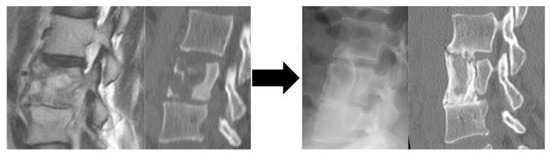

Figure 3.

Representative case of Group C with planned ASF plus posterior instrumentation A Preoperative CT: Bone destruction at the T11 and T12 vertebrae. B Immediate postoperative X-ray: Trans-extrapleural anterior scraping and iliac bone grafting with simultaneous posterior instrumentation. C Postoperative CT: Bone fusing was achieved at 1 year postoperatively. Abbreviation: CT, computed tomography; T, thoracic; ASF, anterior spinal fusion.